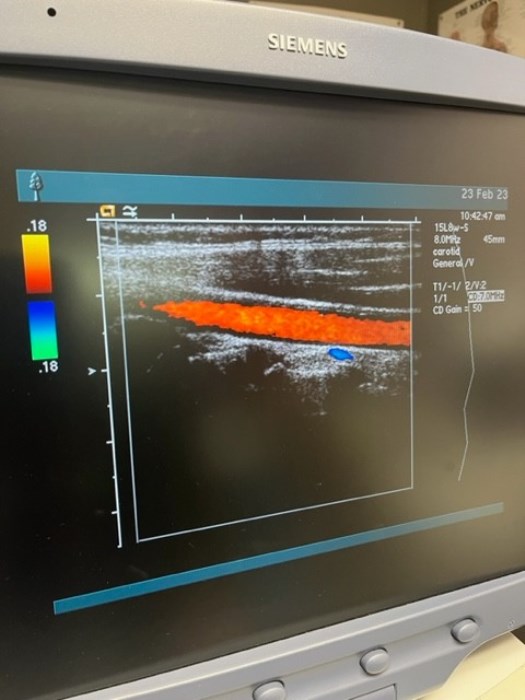

Siemens Sequioa Ultrasound

Pre-owned. In good working condition. Shown as is. Siemens Sequoia Ultrasound. DOM: 2006

Probes: 15L8w, 4V1, 10V4, 6L3, 4C1